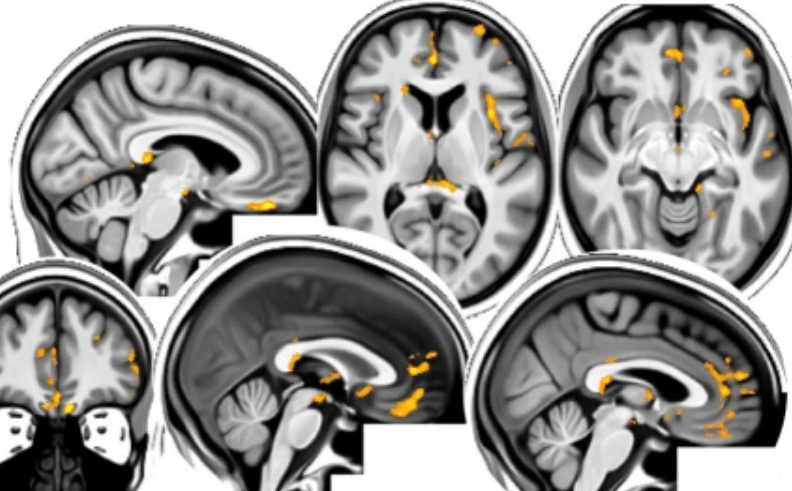

Do milder cases of COVID-19 infection produce changes in the brain?